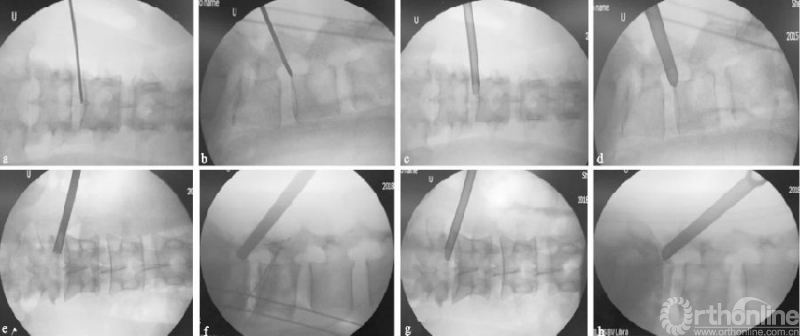

向上游离的腰椎间盘突出症由于没有上关节突的阻挡,一般通过水平穿刺或向上稍倾斜角度的穿刺,不需要行关节突成形,利用工作套管的活动度及带角度的髓核钳,可相对容易摘除椎间盘(见图4a-d);而对于向下游离的腰椎间盘突出症,要根据游离物的大小及方向,来行适当的关节突成形以扩大偏下方的椎间孔区,以顺利摘除椎间盘,减少残留可能(见图4e-h)。

(a)(b)L4/5节段向上游离型突出穿刺置管透视图,其中(a-b)为一级导杆定位图;(c)(d)工作通道放置图;(e-h)L4/5节段向下游离型突出穿刺置管透视图,其中(e-f)为保护套管下环锯行FP图;(g)(h)工作通道放置图

图4 L4/5节段游离型突出穿刺置管图